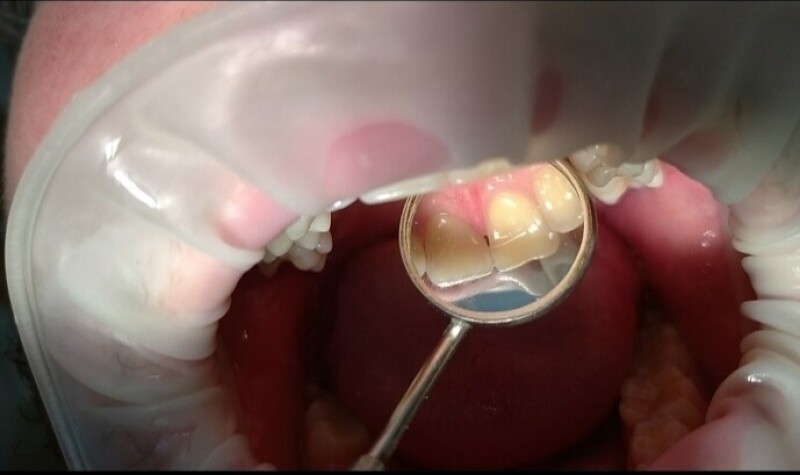

Професійна гігієна порожнини рота – це комплекс заходів, які забезпечують видалення зубного каменю і нальоту на зубах та язику.

- зняття зубних каменів ультразвуковим скелером;

- чищення м’якого нальоту методом Air-Flow;

- полірування та шліфування зубів абразивною пастою.